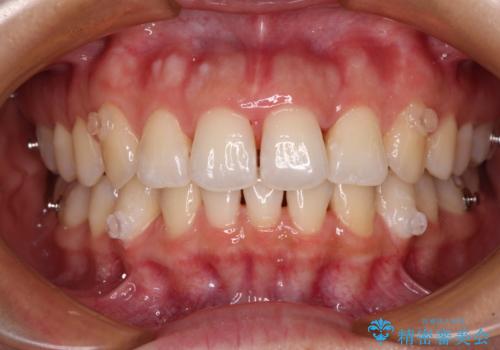

捻れた前歯をインビザラインで整える

- 捻れた前歯が飛び出しており、口が閉じにくいとのことで来院された患者様です。

出っ歯というわけではないものの、前歯の捻転により口唇が押し出されている状態でした。

親知らずを抜去し、歯列全体を後方に移動させつつ、IPR(歯と歯の間を削る)でスペースを獲得し、インビザラインを用いて叢生を解消しながら前歯の突出を改善することとしました。

骨格的に上下正中がずれていたため、奥歯がしっかりと噛み合うか心配でしたが、ずれているなりに、しっかりとした咬み合わせとなりました。